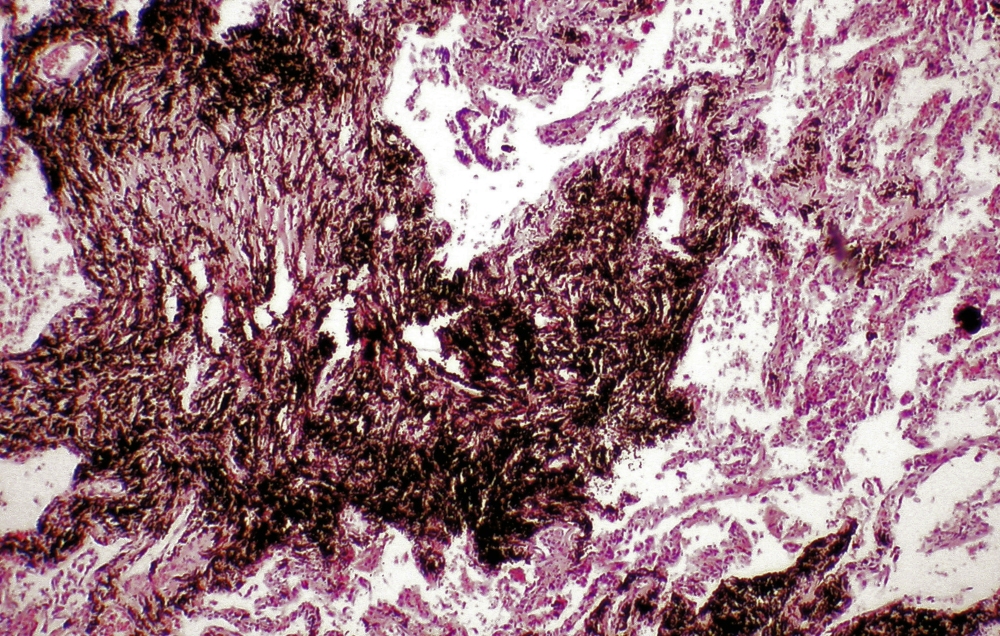

Steinstaub aus dem Bergbau

Bergarbeiter Bronchitis ist als Berufskrankheit anerkannt und hat offiziell die Nummer 4111, heißt „Chronisch obstruktive Bronchitis oder Emphysem”

Chronische obstruktive Bronchitis oder Emphysem von Bergleuten unter Tage im Steinkohlebergbau bei Nachweis der Einwirkung einer kumulativen Dosis von in der Regel 100 Feinstaubjahren ((mg/cbm) X Jahre)

Dabei handelt es sich um die Besonderheit, daß röntgenologisch ein Bergarbeiteremphysem eine Silikose verdecken kann.